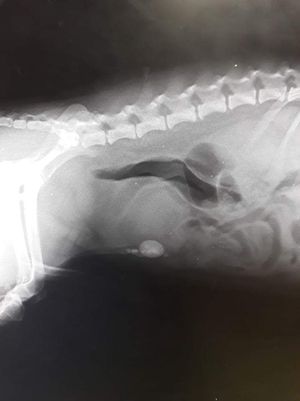

Urethral stones

Stones

Dog

Ureter

Rtg